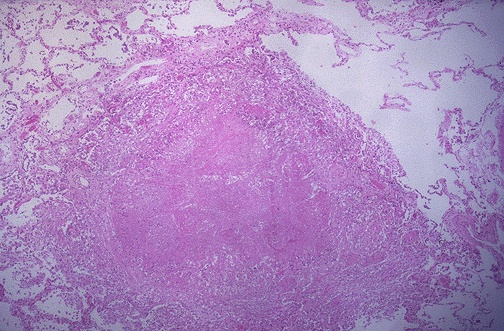

Image 11.4

The low power microscopic appearance of the lung is shown here.